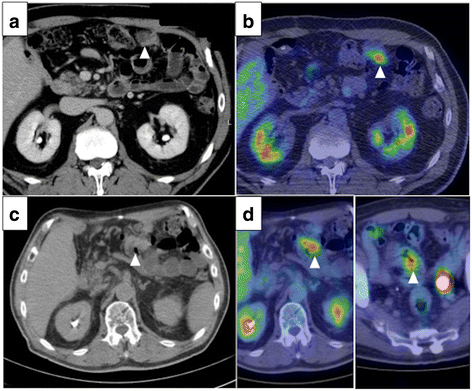

Tumor cells positive for at least 3 of these 4 proteins were regarded as originating from the colorectum. It is reported that CK7 was positive associated with ulcerative colitis (UC)-associated neoplasms [44]. A new prognostic staging system for rectal cancer. In our case, the immunohistochemistry of our patients cervical biopsy and surgical specimen showed a CK7-positive/CK20-negative expression pattern (Fig.

The authors thank Dr. Atsushi Koyama (Sendai Open Hospital, Sendai, Japan) for providing the medical information. c Pelvic magnetic resonance image of a T2-enhanced sagittal section showing an irregularly enlarged uterine cervical tumor (red arrow). (e) H&E staining of well differentiated CRC with scattered distribution of single cancer cells (H&E, 10). var thismailbody11 = ""; thismailbody3 = thismailbody1; var thismailbody2 = ""; Furthermore, both CA19-9 and CEA rapidly returned to levels within normal limits after the patient underwent radical hysterectomy (Fig. Cytoplasmic immunoreactions for CK7, CK20, villin and cadherin 17 IHC staining were considered as positive and CDX2 IHC staining showed dense positive brown nuclear immunoreactions. However, performing a histopathological diagnosis that discriminates between a colorectal adenocarcinoma metastatic to the cervix and a primary cervical adenocarcinoma with colonic differentiation is difficult [9]. Cytokeratin 7/20 and mucin core protein expression in ulcerative colitis-associated colorectal neoplasms. After washing with PBS, these slides were incubated overnight with mouse anti-CK7 (MXB Biotechnologies Inc., Fuzhou, China, Kit-0021, 1:100 dilution) at 4C. Sullivan LM, Smolkin ME, Frierson HF, Galgano MT. Internal and digital examinations were negative for parametrial and rectal involvement. ICC and western blotting also confirmed that LoVo and HCT116 PGCCs and their daughter cells had higher CK7 expression than the control cells. Department of Pathology, Tianjin Union Medical Center, Tianjin, P.R. Zhang S, Mercado-Uribe I, Hanash S, Liu J. iTRAQ-based proteomic analysis of polyploid giant cancer cells and budding progeny cells reveals several distinct pathways for ovarian cancer development. We previously reported that PGCCs induced by CoCl2 could generate daughter cells with strong migratory and invasive abilities. Comprehensive evaluation of CDX2 in invasive cervical adenocarcinomas: immunopositivity in the absence of overt colorectal morphology. 1B-a and -b) and the invasion front (Fig. However, CDX2 expression may also be positive in adenocarcinomas of the upper gastrointestinal tract and other lesions, including those of the uterine cervix. Zhang S, Mercado-Uribe I, Sood A, Bast RC, Liu J. Coevolution of neoplastic epithelial cells and multilineage stroma via polyploid giant cells during immortalization and transformation of mullerian epithelial cells. (d) CK7 positive staining of (c) (IHC, 10). Furthermore, hyperplastic polyps and serrated adenoma in the colorectum yielded positive staining results for CK7 and canalicular adenoma yielded negative results for CK20. 1. The Journal of cell biology. 2007;16(Suppl 1):S7-9, 47. (b) Few PGCCs from LoVo (black arrows) yielded positive IHC staining results for CK7 before CoCl2 treatment (IHC, 10). CK7 positive cells were not uniformly distributed and mainly were distributed at the edge of cancer nests, the invasion front, tumor buds, as single stromal PGCCs, in intravascular tumor emboli, and in the micropapillary pattern. Tumor budding and the micropapillary pattern may both be derived from PGCCs and their budding daughter cells [7]. CDX2, Cecal cancer, Cervical metastasis, Cytokeratin 7, Cytokeratin 20, Immunohistochemistry, Tumor marker. 2A-f). CDX2, a highly sensitive and specific marker of adenocarcinomas of intestinal origin: an immunohistochemical survey of 476 primary and metastatic carcinomas. 1A-c and -d), and poorly differentiated (Fig. After CoCl2 treatment, the PGCCs and their daughter cells of LoVo and HCT116 yielded positive results in CK7 ICC staining. Jass JR. Molecular heterogeneity of colorectal cancer: Implications for cancer control. Kirchner T, Muller S, Hattori T, Mukaisyo K, Papadopoulos T, Brabletz T. et al. The Institutional Review Board of Tianjin Union Medical Center approved this study, and patient anonymity was maintained. The evidence from our rare case was consistent with a metastasis to the uterine cervix that originated from a distant tumor. Zhang D, Yang X, Yang Z, Fei F, Li S, Qu J. et al. 3A-c and -f). 2015;31:219-22, 26. Onco Targets Ther. PGCCs in CRC (H&E, 10). Virchows Archiv: an international journal of pathology. It has been reported to appear in cancers of the breast, bladder, lung, pancreas, ovary, urothelial tract, and stomach [26-29] and is associated with tumor differentiation, lymph node and distant metastasis, and lymphovascular tumor emboli [7, 17]. (b) LoVo PGCCs survived the treatment of 300 M CoCl2 for 48 h (black arrows, 10). 4d), p16, estrogen receptor, progesterone receptor, vimentin, calretinin, and cluster of differentiation-10 expression. After recovery from CoCl2 treatment, PGCCs could generate daughter cells via budding (Fig. (d) Morphological characteristics of HCT116 cells before CoCl2 treatment (10). CK7 positive CRCs from more than one thousand cases in our hospital were used to study the clinicopathological significance and 107 cases of CK7 negative CRCs were used as a randomized controlled comparison. 2018;11:264-73, 20. The diffuse distribution of CK7 positive tumor cells was often present in poorly differentiated CRCs. a cancer journal for clinicians. Verdu M, Roman R, Calvo M, Rodon N, Garcia B, Gonzalez M. et al. Dukes CE, Bussey HJ. In pathology, PGCCs were the key contributors to cellular atypia and were associated with the malignant grade of tumors. Primary cancers of the cecum are anatomically less likely to invade the uterine cervix than primary rectosigmoid cancers. Tumor cell morphology at the invasion front is different from that in the tumor center. BMC cancer. In poorly differentiated CRCs, almost all tumor cells were CK7 positive (Fig. 2014;14:576, 21. com. The patient is currently receiving adjuvant chemotherapy and to date is without evidence of recurrent disease.